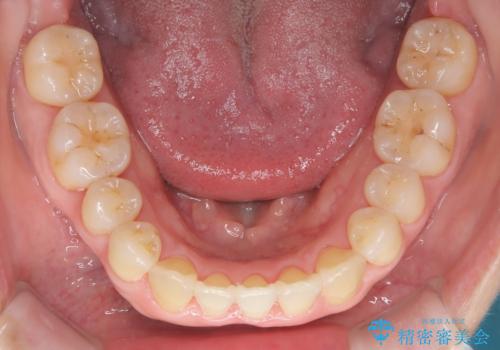

- 前歯の噛み合わせが悪いことを主訴に来院されました。

歯周病も併発していたため、歯牙への負担が少なくなるように治療計画をたて、インビザラインにて治療を完了しました。

矯正開始前に半年間、歯周治療を行ってからインビザラインを装着しています。